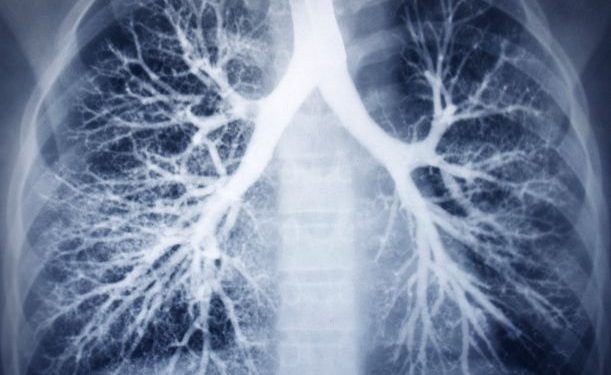

Lung – congenital defects symptoms vary depending on the condition and what parts of the lung and airways are not developing normally. Sometimes, they are mild and don’t cause any problems or other symptoms at all; in other cases, they can be serious and life-threatening.

The most common congenital lung abnormality is CPAM (congenital pulmonary airway malformation). It affects 1 in every 4,000 babies born each year and involves cystic lung lesions or masses that form on one of the lungs. These noncancerous masses are most common in the right lung, but can occur anywhere on the lungs.

Other congenital lung conditions include bronchial atresia, congenital lobar emphysema, and pulmonary sequestration. These conditions can be very serious, but they are also rare.